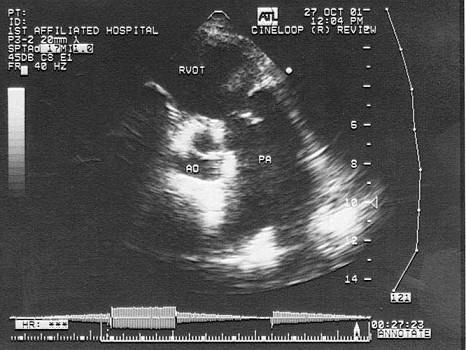

问题 患者老慢支疾病多年,该病例最有可能诊断?(?)

选项 A.原发性肺动脉扩张 B.右流增宽 C.肺动脉瓣关闭不全 D.肺动脉高压 E.动脉导管未闭

答案 D